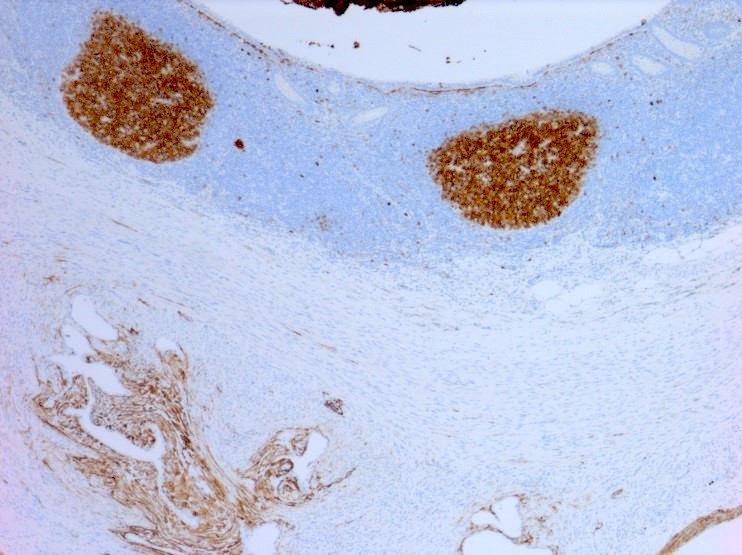

Microscopic (histologic) images

Positive stains

- CD10 is positive in endometrial stroma

- ER, PR and PAX2 are often positive in endometrial glands and stroma (Am J Surg Pathol 2013;37:1342)

Molecular / cytogenetics description